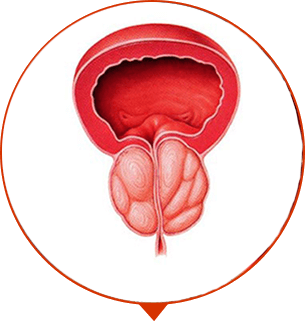

ADENOM DER PROSTATA

Gewebsvermehrung der Prostata, Bildung des Tumors und “der Knoten”

Die Zusammensetzung von Prostalium+ spricht für sich. Das ist ein absolut sicheres Mittel für die Männer der älteren Generation. Dank einzigartiger Formel und Konzentration der aktiven Komponenten, der Vitamine entfernt die Entzündung, regeneriert die Erektion, Prostatitis kehrt nicht zurück. Der Männerkörper arbeitet wie schweizerische Uhr.

KOMPLEXE GENESUNG

Intensive Wirkung auf die Gewebe der Prostata, allgemein kräftigende Wirkung. Es gibt mehr Kräfte, Energie, die gefestigte Libido, ausgezeichnete Potenz